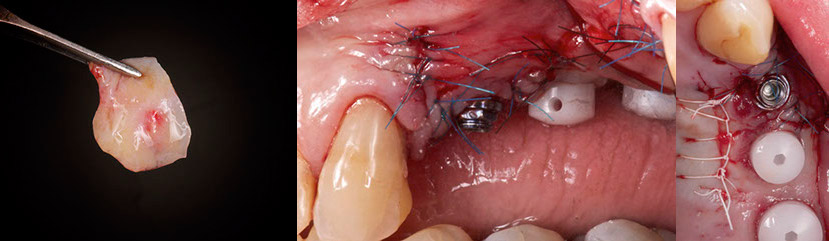

First of all, the connective tissue graft was harvested from the palatal. 4/0 PTFE sutures were used to suture the wound.

A flap with beveled distal and mesial vertical releasing incisions was raised, avoiding the canine and the adjacent implant. Several incisions were performed apically in the periosteum so the flap could be mobilized coronally and cover the recession.

GBR was performed utilizing Bio-Oss (Geistlich, Switzerland) mixed the autologous bone (50/50) and a collagen membrane Creos (Nobel Biocare). The membrane was cut in two pieces and used to cover the biomaterial, one was placed vertically and the other horizontally so it can stabilize the biomaterial.

The connective tissue was then sutured to the implant neck with 5/0 monofilament sutures and covered with the flap.